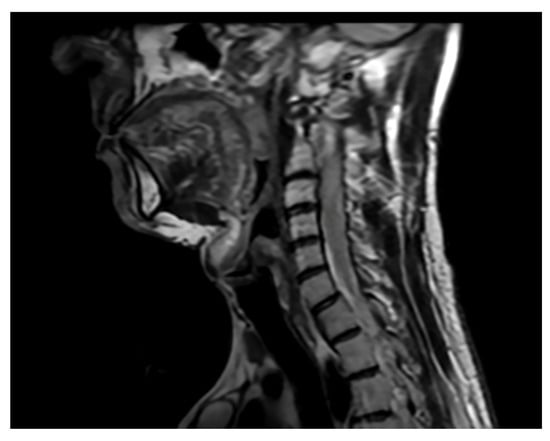

Case Report